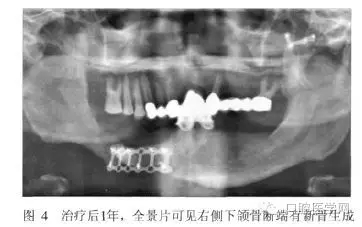

術(shù)后2周和半年進(jìn)行兩次重襯。治療后半月、3月、6月、1年后復(fù)診,患者的頜面部外貌明顯改善,咀嚼功能提高,義齒使用效果良好(圖3)。全景片示骨斷端有新骨生成(圖4)。

從患者修復(fù)后1年的效果來看,義齒臨床效果良好,X線片示斷端骨密度升高。筆者認(rèn)為對于類似長期骨愈合不良的斷端,通過適宜的功能刺激及義齒功能狀態(tài)下維持骨斷端的穩(wěn)定,可能有利于促進(jìn)骨的生長和愈合。